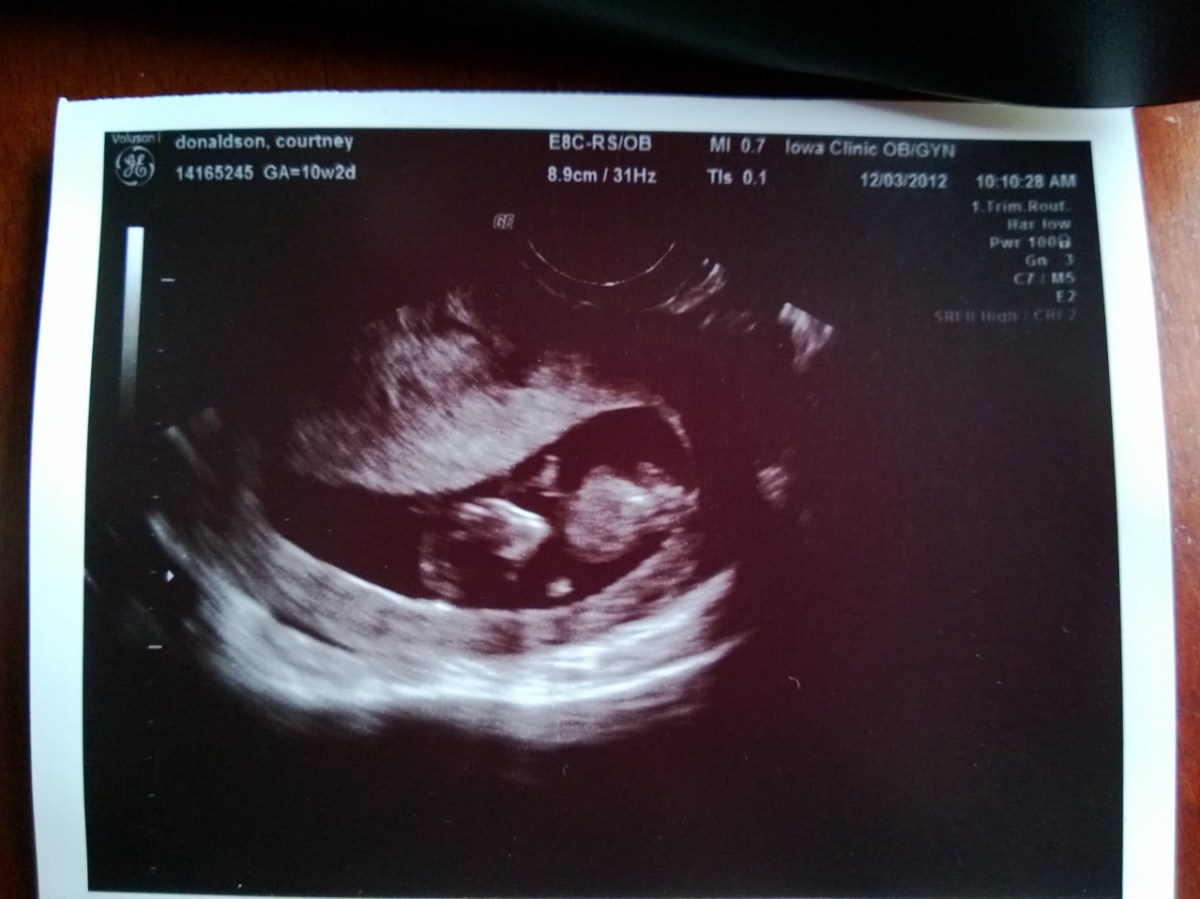

WP_20121203_007 December 3, 2012 by Courtney Leave a comment ← Previous Image Next Image → 10w2d- CRL of 3.91 cm Like Loading...